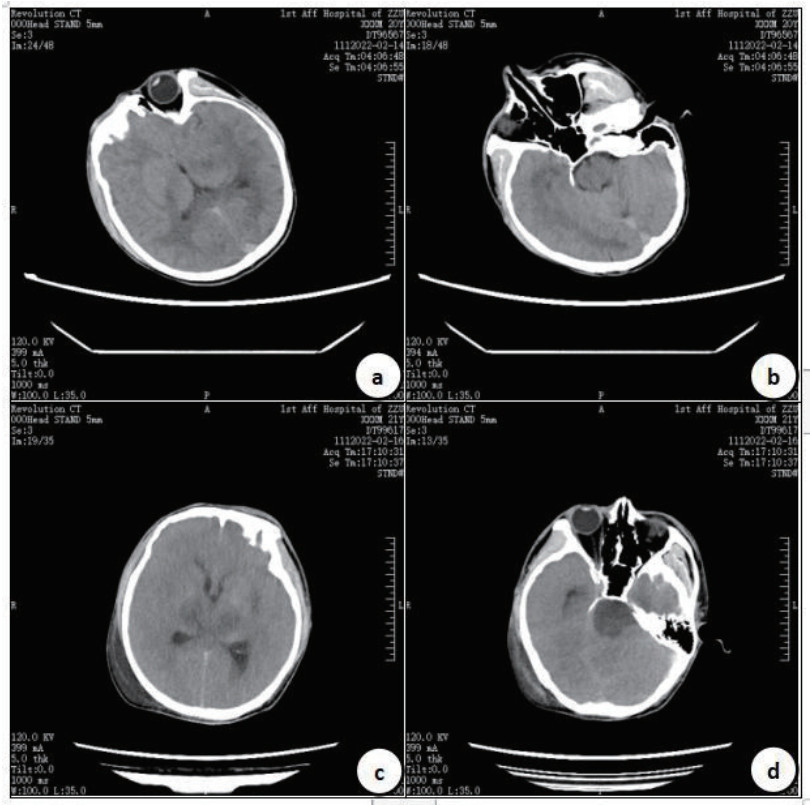

|

| 入院第7天的MRI显示,T1WI(1a和1c)、T2WI(1b和1d): 胼胝体压部、双侧丘脑、双侧基底节区、脑干异常信号。第60天、第105天MRI显示,T1WI(2a和2c、3a和3c)、T2WI(2b和2d、3b和3d): 左侧额叶、右侧顶叶见少许点片状稍长T2信号影,黑水像呈稍高信号。桥脑及中脑可见对称性斑片状长T1长T2信号影,黑水像中心呈高信号,边缘环绕低信号。 图 2 病例2的MRI结果 Fig 2 MRI results of Case 2 |